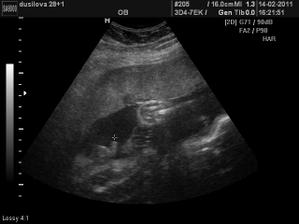

Ve 28tt nám paní doktorka na 3D ukázala krásnýho chlapečka i s jeho pýchou 🙂 Na 99,9% čekáme chlapečka - Tadeáška. Jsem hrozně moc šťastná, že nám vyšlo to co jsme od začátku chtěli - mít starší dcerku a mladšího syna! Tak teď už to jen zdárně doklepat do konce 😀